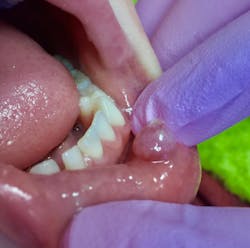

Clinical assessment on the lower lip revealed:

- 7 mm-plus soft, exophytic, dome-like lesion

- Normal lip color

- Fluid filled with a slightly red base

- No pain, but the patient was having a hard time eating due to position and size of lesion